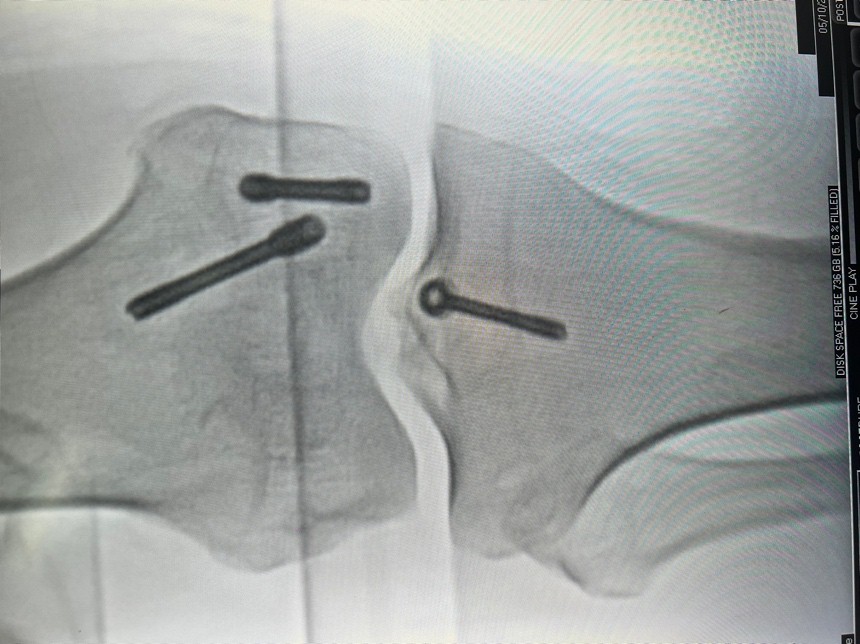

Careful dissection was performed to protect the popliteal neurovascular bundle, including the tibial nerve and popliteal vessels, which were gently retracted throughout the procedure. The PCL avulsion fracture was identified, and the fragment was cleared of soft-tissue interposition to ensure an optimal reduction. Under fluoroscopic guidance PCL fragment was reduced anatomically and temporarily stabilized using Kirschner wires. A definitive fixation was achieved using a partially threaded cancellous compression screw with a washer from the avulsed fragment to the tibia.

The medial Hoffa fracture was also addressed during the same procedure. The fracture was anatomically reduced and temporarily stabilized with Kirschner wires. Two Herbert screws were then inserted, one in an anterior–posterior direction and the other in a posterior–anterior direction, ensuring compression and stabilization of the fracture plane (Fig. 4a and b).

Figure 4: (a and b) Intraoperative fracture fixation anteroposterior and lateral images.

This opposing screw configuration provided robust fixation, and intraoperative fluoroscopy was used to ensure accurate alignment and the adequacy of fracture reduction.